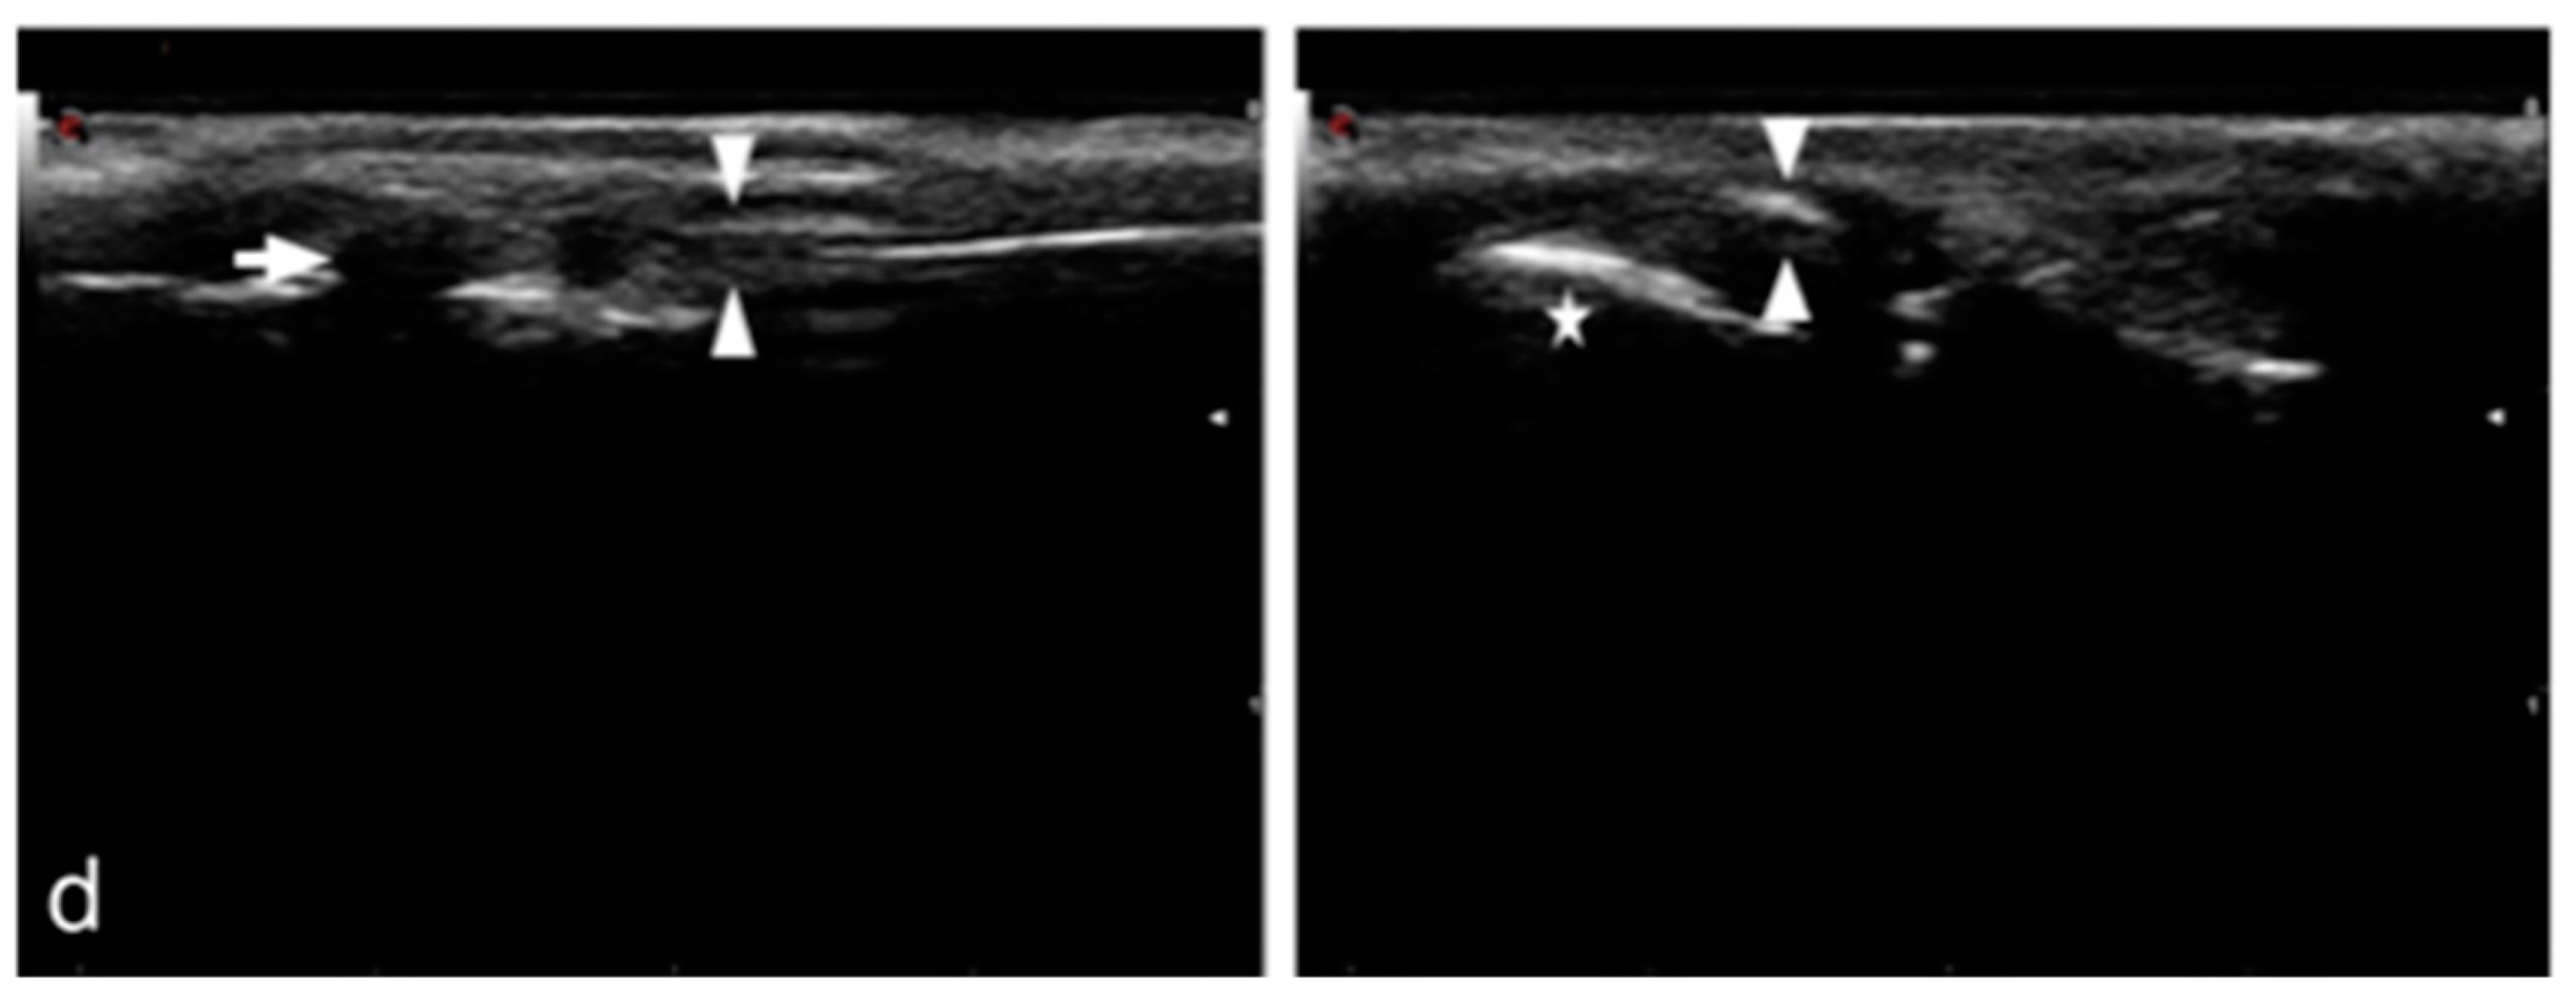

2.2.3. Ultrasonographic Examination

2.3.3. Ultrasonographic Examination